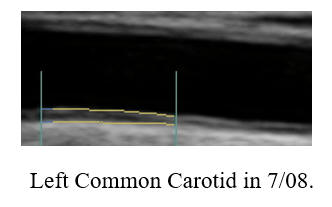

Carotid Intima-Media Thickness (IMT) is discussed in detail elsewhere on this

site. IMT is not plaque, but rather the thickness of the artery wall

(endothelial and muscular layers) within a normal appearing region of the common

carotid artery. IMT is a systemic measurement, the "staging ground" of

plaque formation. IMT reflects the status of your